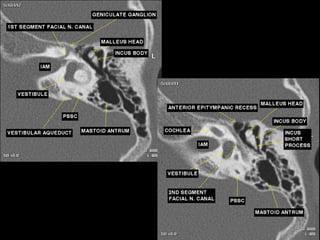

CT Temporal Bone Search Pattern with selected images :

Use both axial and coronal CT

images

Otic capsule:

•Superior semicircular canal (SCC)

•Posterior SCC (P)

•Lateral SCC (L)

•Vestibule (v)

•Aditus ad antrum (A)

•Cochlea

•Modiolus (mo)

•Basal turn (b)

•Middle turn (m)

•Apical turn

•IAC

•Facial n.

•labyrinthine segment (Fnl)

•geniculate segment

•tympanic segment

•Vestibular aqueduct